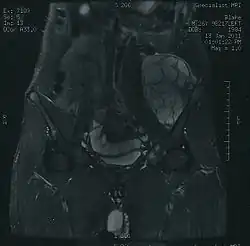

Imaging studies – including radiographs ("x-rays"), computerized tomography (CT), and magnetic resonance imaging (MRI) – are often used to make a presumptive diagnosis of chondrosarcoma.[9] However, a definitive diagnosis depends on the identification of malignant cancer cells producing cartilage in a biopsy specimen that has been examined by a pathologist. In a few cases, usually of highly anaplastic tumors, immunohistochemistry (IHC) is required.

There are no blood tests currently available to enable an oncologist to render a diagnosis of chondrosarcoma. The most characteristic imaging findings are usually obtained with CT.[10]

- ^ CT scan and gross pathology of a chondrosarcoma 2012-12-18